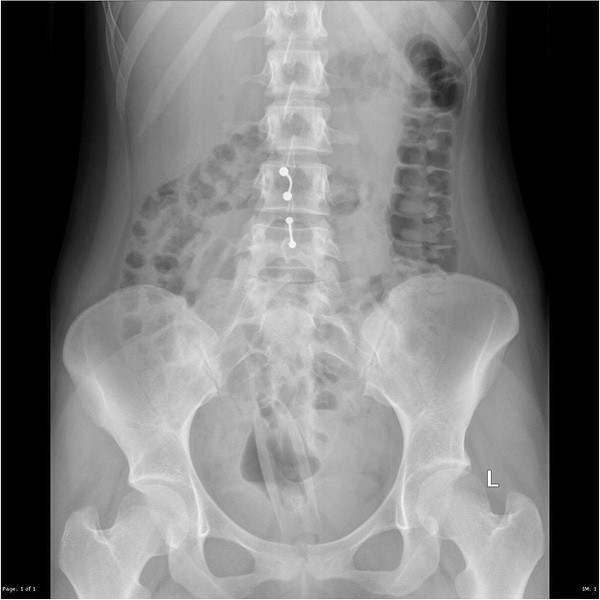

Se pensavate di poter correre al pronto soccorso con un attaccapanni intrappolato nel colon e bearvi del segreto professionale medico-paziente abbiamo delle brutte notizie per voi. Gli addetti alle radiografie si divertono un mondo a rendere pubbliche le lastre dei vostri addomi, specialmente se custodiscono oggetti insoliti utilizzati per sollazzarvi in segreto.

Ecco una splendida galleria di immagini ai raggi-x che raccontano silenziosamente di voglie improvvise, trasgressione, tentati giochi erotici poco riusciti, ma sopratutto, infinito imbarazzo. Fanno proprio tenerezza questi poveri sventurati, per la maggior parte uomini di mezza età, che infondo volevano solo divertirsi un po’. Non avete mai tentato di infilare una melanzana nel vostro ano? Ah beh, allora sapete tutto voi.

Molto banalmente un vibratore, con motore in metallo facilmente individuabile.